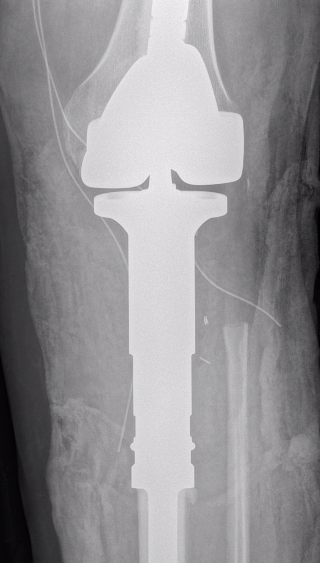

Wide Resection

A. Hemicortical resection and posterior hemicortical allograft reconstruction

- no chemotherapy if low grade

- hemicortical resection and hemicortical allograft reconstruction

- 22 cases (6 parosteal, 6 peripheral chondrosarcoma, 10 adamantinoma)

- all allografts incorporated

- 6/22 (27%) patients had a fracture of the remaining host hemicortex

- good excellent functional outcome in 21/22 patients